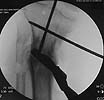

Pt was 10 yrs s/p open tibia fx treated in a cast w/ IR, varus, 2 cm short, and recurvatum. He has done well post op.

18 mos postop